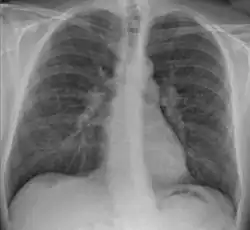

| Chest X-ray showing the typical nodularity of sarcoidosis, predominantly in the hila of the lungs. | |